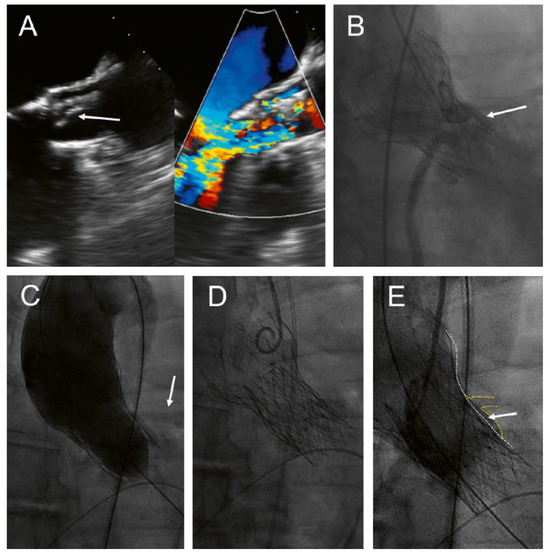

Direct His bundle pacing has recently attracted interest as a more physiological alternative to right ventricular or biventricular stimulation. The advent of new tools has facilitated the implantation procedure. This report relates our initial experi...